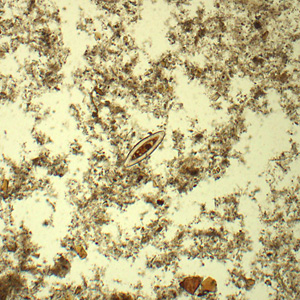

Case #433 – December, 2016

A 34-year-old male from Louisiana presented with abdominal discomfort. A stool specimen was collected in 10% formalin and a formalin-ethyl acetate (FEA) concentration was performed. A wet mount smear was prepared from the sediment and examined for ova and parasites (O & P). Figure A was captured at 100x magnification; Figures B–D were captured at 400x magnification. The objects of interest measured 155-165μm by 48-55μm. What is your diagnosis? Based on what criteria?

Figure A